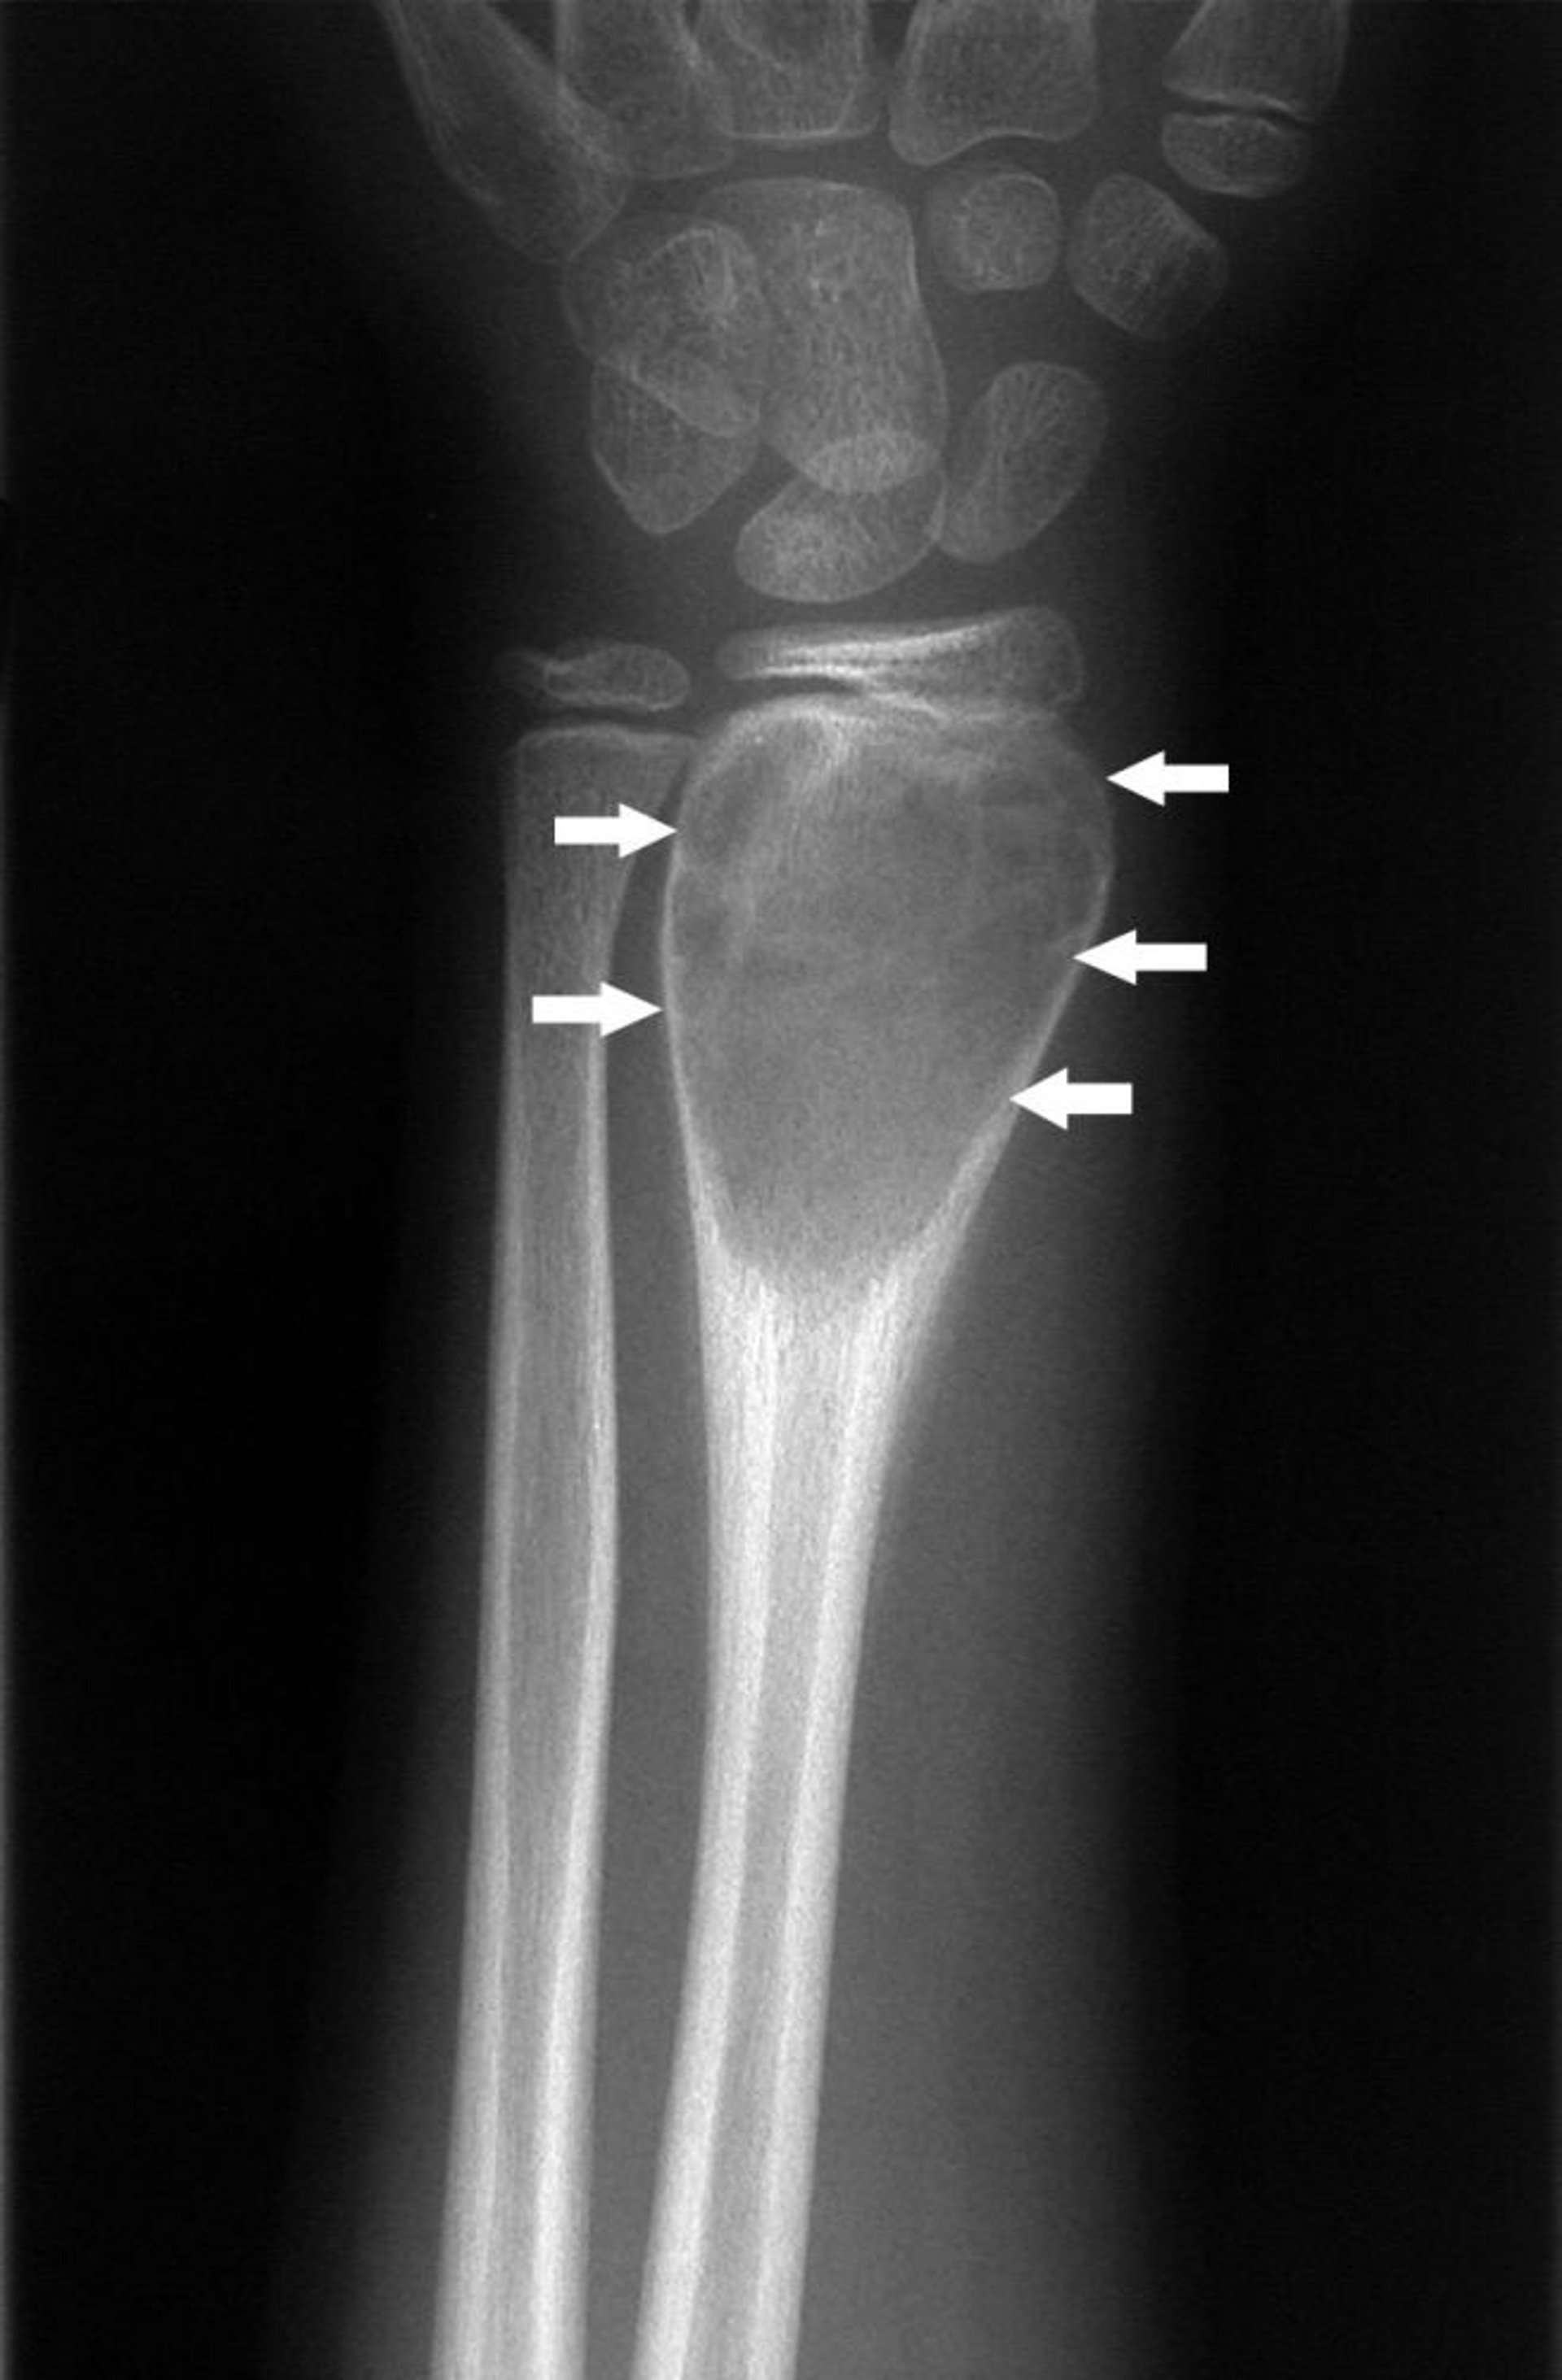

الكيساتُ العظميَّة الأُمْ دمِّيَّة في المعصم

تُظهر هذه الصورة الشعاعية لمعصم اليد كيسة عظمية أُم دميّة (اتجاه الأسهم).